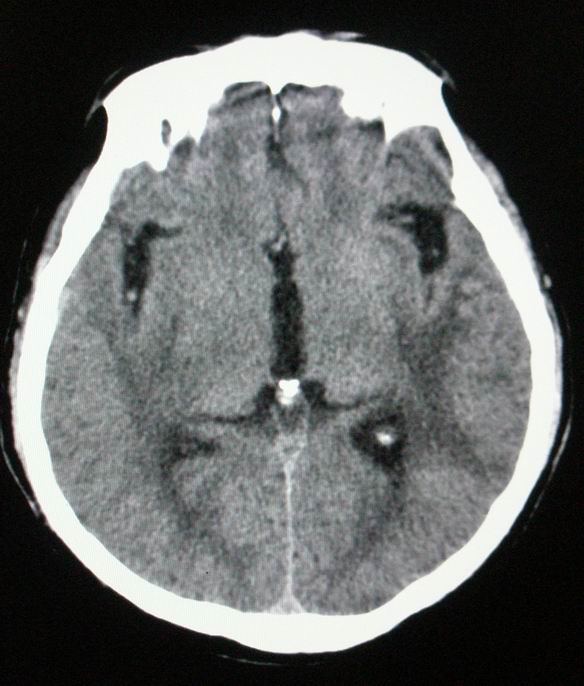

以下是引用随光逐影在2008-4-5 7:46:00的发言:[br]1)考虑为:多发性脑转移瘤。建议:行进一步检查。2)多发性腔隙性脑梗塞。3)脑白质病。4)脑萎缩。

以下是引用zjzjr在2008-4-5 9:00:00的发言:[br]1.双侧颞叶占位性病变,考虑为转移瘤可能性大。[br]2.左侧基底节区陈旧性腔隙性脑梗塞。[br]3.脑白质病。建议mri进一步检查。

以下是引用xuhuihong在2008-4-5 0:59:00的发言:[br]1.双侧颞叶占位性病变,考虑为转移瘤可能性大。[br]2.左侧基底节区陈旧性腔隙性脑梗塞。[br]3.脑白质病。建议mri进一步检查。

以下是引用形影不离在2008-4-4 23:29:00的发言:[br]1.双侧颞叶占位性病变,考虑为转移瘤可能性大。[br]2.左侧基底节区陈旧性腔隙性脑梗塞。[br]3.脑白质病。